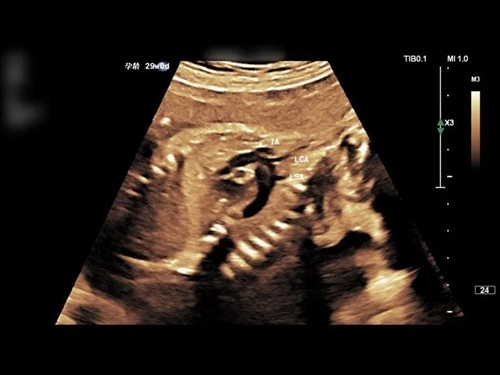

在半島地區(qū),青島市婦女兒童醫(yī)院產(chǎn)科超聲是響當當?shù)摹敖鹱终信啤薄W鳛獒t(yī)院的特色品牌亞???,這里每年要完成 10 余萬人次的胎兒超聲檢查,其中 2.5 萬余人次的產(chǎn)前系統(tǒng)超聲篩查,診斷病例數(shù)量及畸形種類均居山東省首位。

這份專業(yè)底氣,來自于科室對每一個生命的極致負責?!疤阂嗍腔颊摺薄?正是基于這樣的理念,今年,科室在原有大排畸的基礎上,新增孕 20-22 周、30-32 周兩次小排畸檢查,與大排畸形成更密集的篩查網(wǎng)絡,像一張細密的防護網(wǎng),把畸形漏診、誤診的風險降到最低。從常規(guī)的 Ⅰ 級到 Ⅳ 級產(chǎn)前超聲檢查,到胎兒超聲心動圖、中樞神經(jīng)系統(tǒng)專項檢查,再到全省最早開展的超聲引導下胎兒宮內(nèi)手術,這里能為孕媽媽提供全周期、全維度的超聲保障。